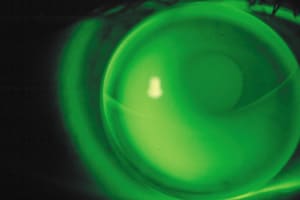

Figure 1. Note whether pupil size is excessively large (left) or small

(right). |

TIP #5 -- Measuring Pupil Size and Dynamics

Many ocular measurements increase patient success with presbyopic designs, but pupil size (Figure 1) is key. First, assess the pupils in normal room lighting with a millimeter ruler or another type of measuring device. Use a white light source at the slit lamp to simulate the smaller pupil size common in bright light conditions. Then use low illumination and a cobalt blue filter to approximate pupil size at night.

These tests reveal whether the patient has a relatively small, normal or large pupil and how reactive it is to changes in lighting conditions. This can help you choose among presbyopic lens types, but it's not as definitive as placing a lens on the patient's eye and evaluating his visual response to changes in lighting.

Today's soft presbyopic designs primarily employ simultaneous vision concepts, with the reading portion usually located in the center of the lens. Thus, a patient who has small pupils will view through an inordinate amount of the reading zone for distance tasks. Conversely, for patients who have large pupils, the distance portion interferes with near vision. In general, designs with center-near adds work better with pupils >5mm, and center-distance adds are advantageous for smaller pupils.